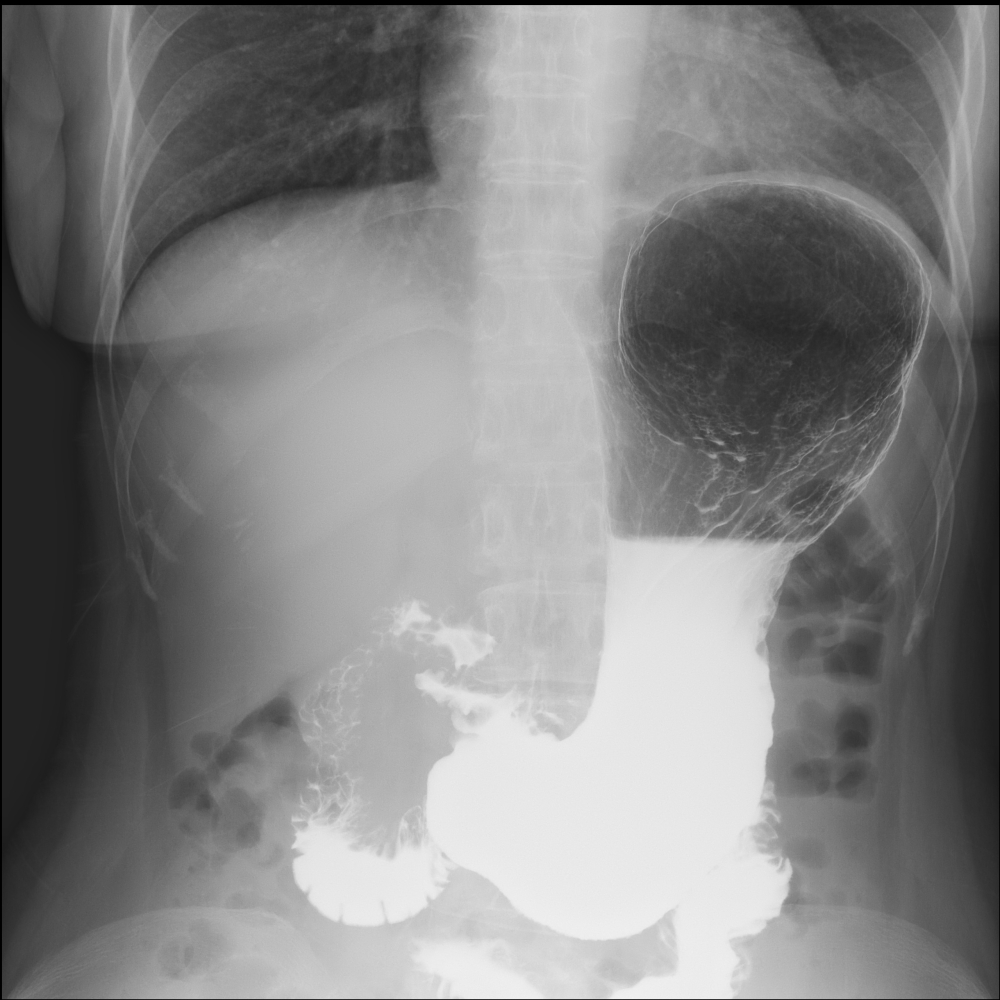

X(エックス)線で透視をしながら、体内の動きをテレビで観察する検査です。

消化器科の胃や大腸の検査(バリウムなどの造影剤を使用した検査や内視鏡検査など)、泌尿器科のステント(膀胱から尿を体外に出すための管)交換など多種多様な検査を行っています。

当院のX線TV装置もフラットパネルを使用しています。 またX線TV室14の装置はX線管球とフラットパネルを 回転させて任意の角度から体内を観察することができます。